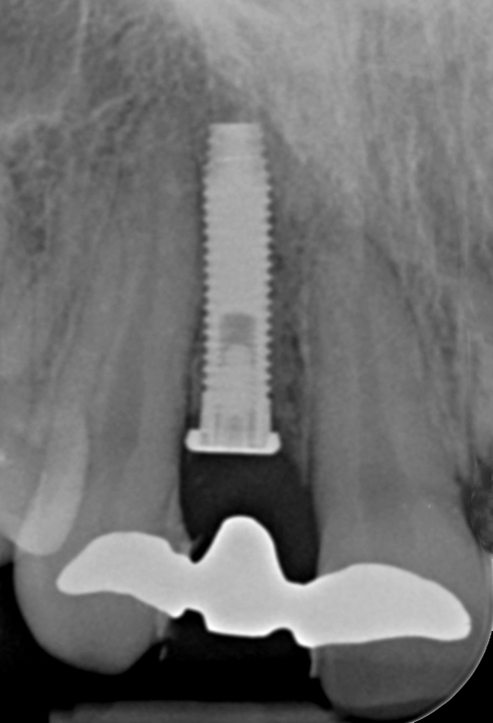

Clinical examination showed 2 mm of buccal recession with a shallow vestibule and absence of keratinized attached gingiva against the crown with 8 mm of circumferential pocketing accompanied by bleeding upon probing (Figure 15 and Figure 16). A periapical radiograph showed a symmetrical vertical osseous defect causing the loss of 50% of the bone around the implant (Figure 17). Because the patient had made a significant investment of time and finances to replace her lost tooth with the implant, she desired that the implant and restoration be retained, if feasible.

Fig 17. Radiograph showed symmetrical infrabony defect affecting 50% of the implant surface.